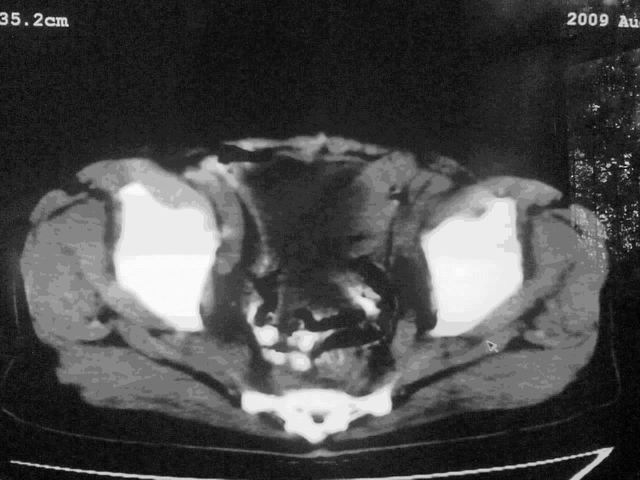

我这个考考大家眼力,看看是升结肠ca还是降结肠ca

下面的是4小时后的,

结肠占位并肝及腹膜后淋巴结转移。